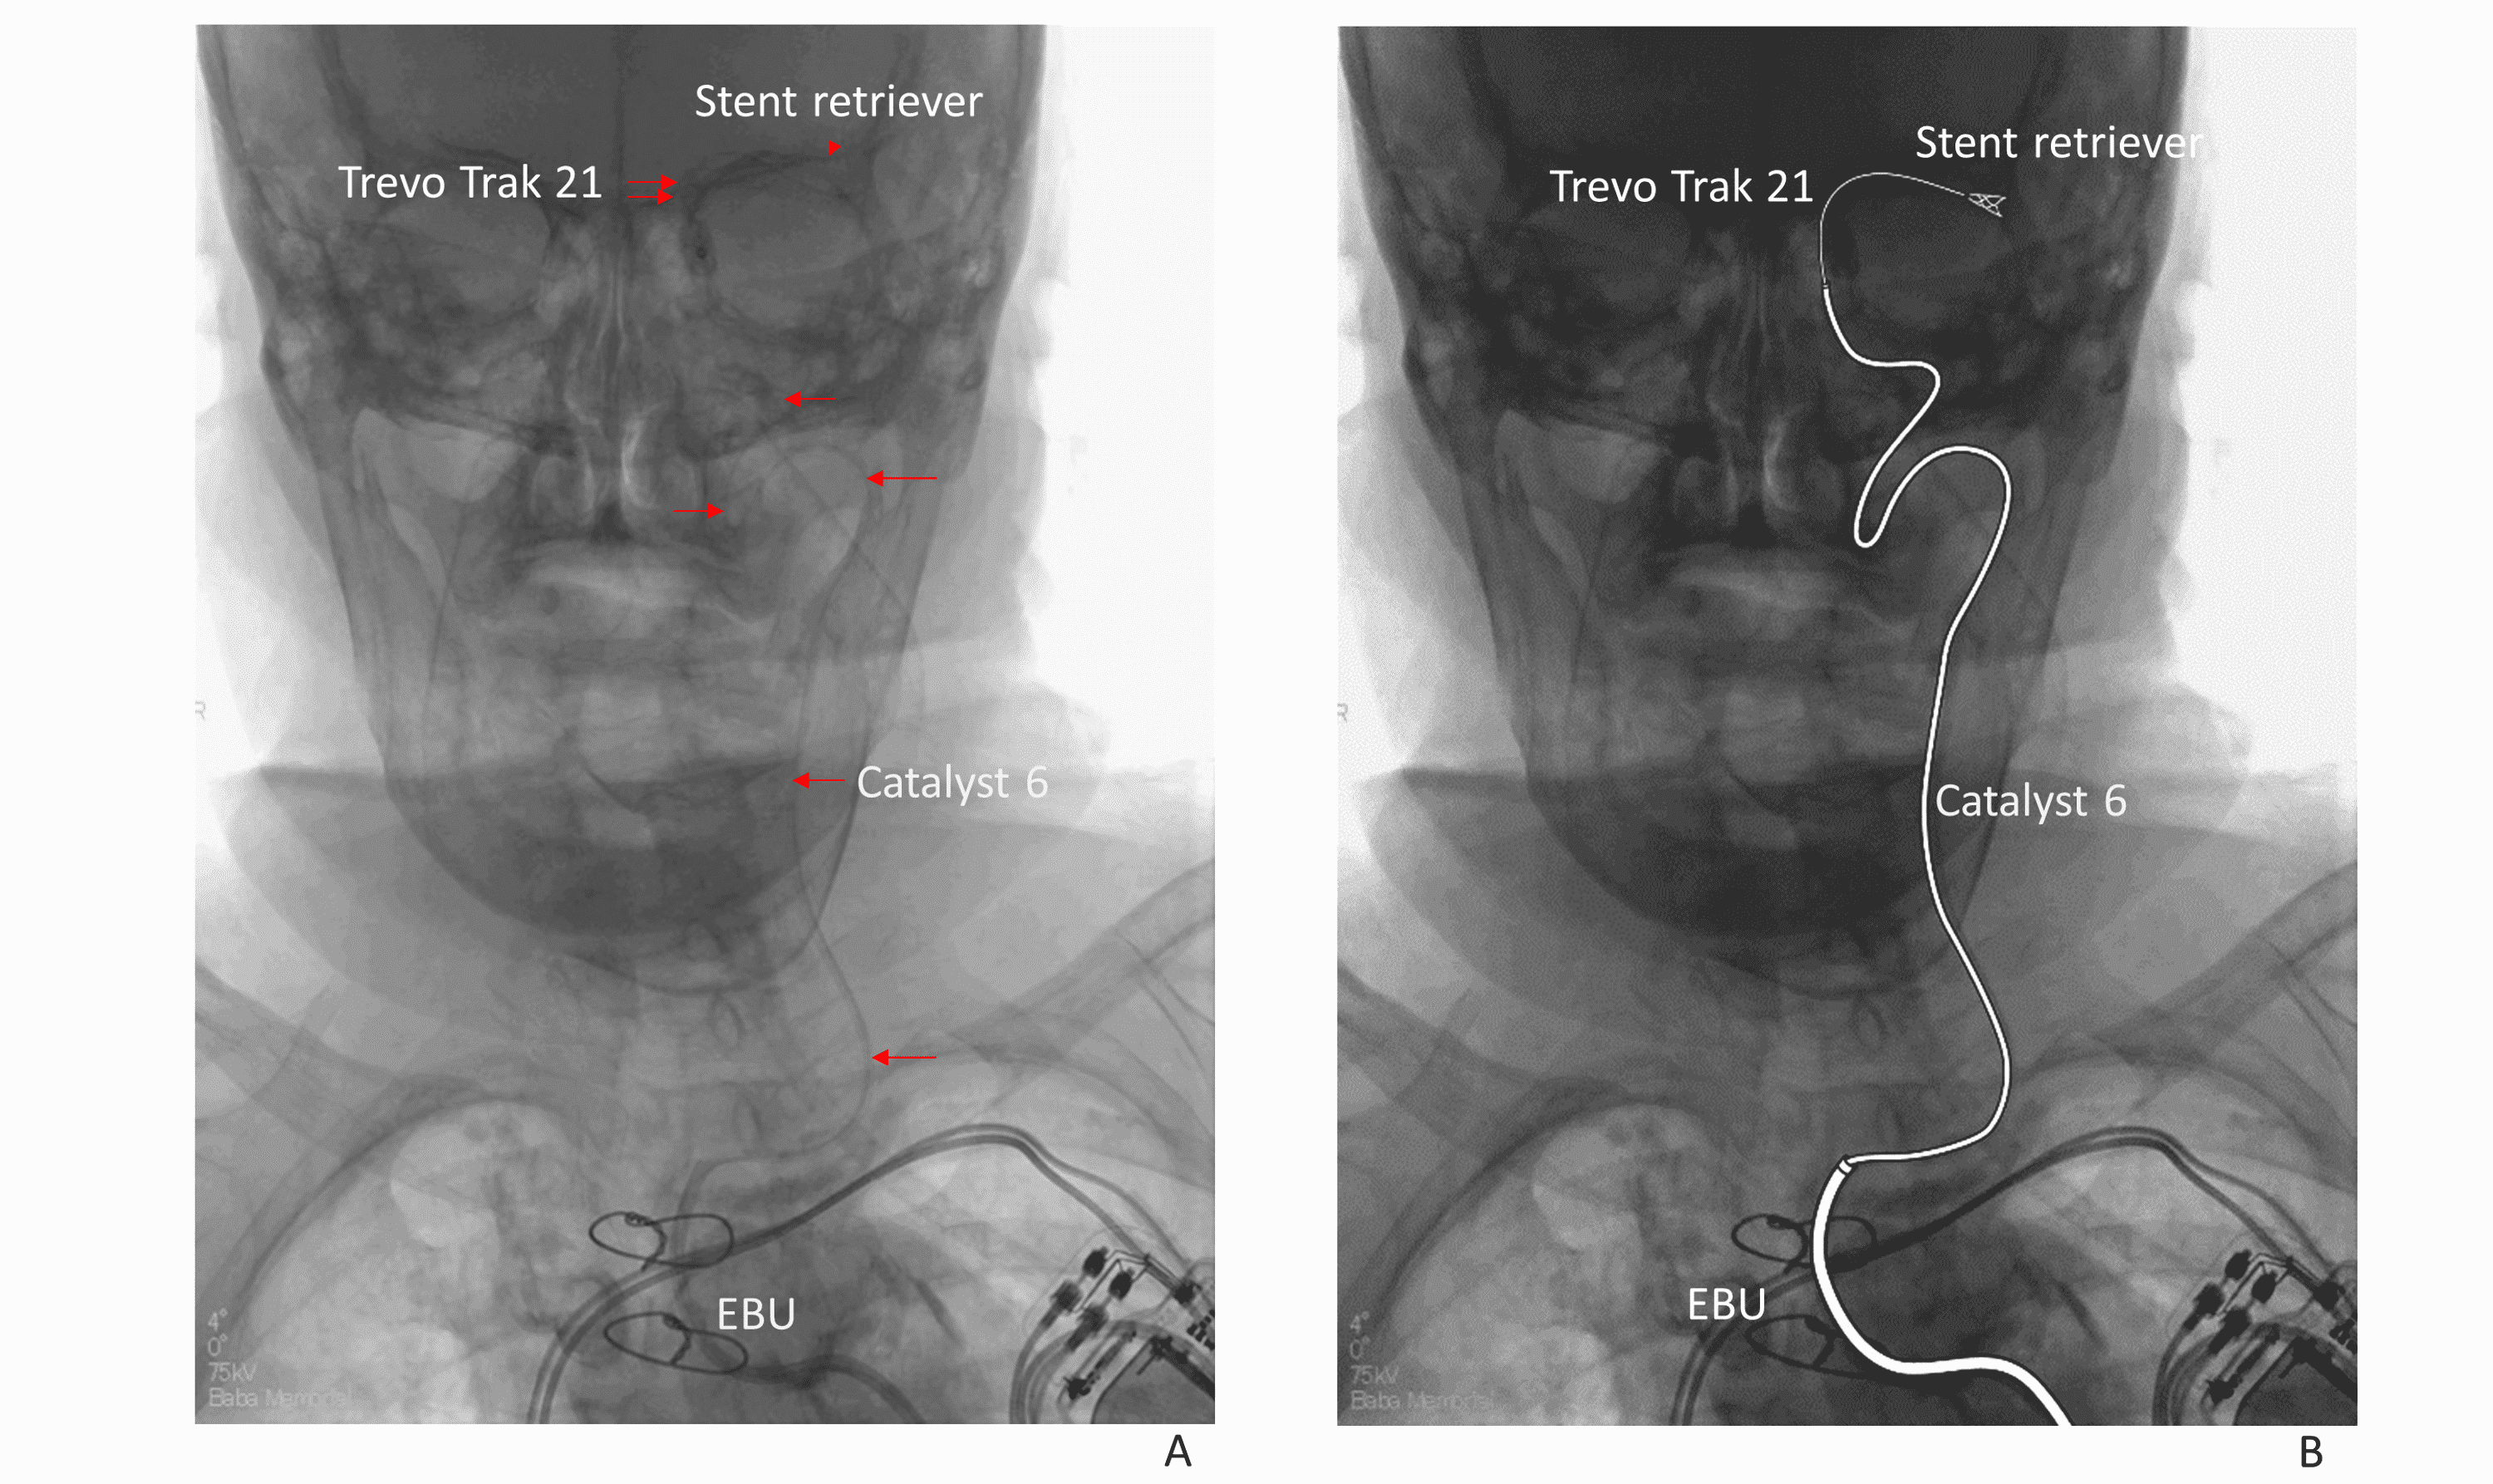

Guiding catheter (EBU) entrapped in right subclavian artery YouTube Ebu Guide Catheter Full Form A guide catheter with a supportive shape should be used, such as the voda/ebu/xb catheters for the left coronary artery, amplatz left. Usual guiding catheters, but adapted to have a good support and specific manipulation to ostial cannulation. 90°), and a reinforced construction (3 vs. An effective and easy manipulate method is introduced with ebu guiding catheter (gc) in this. Ebu Guide Catheter Full Form.